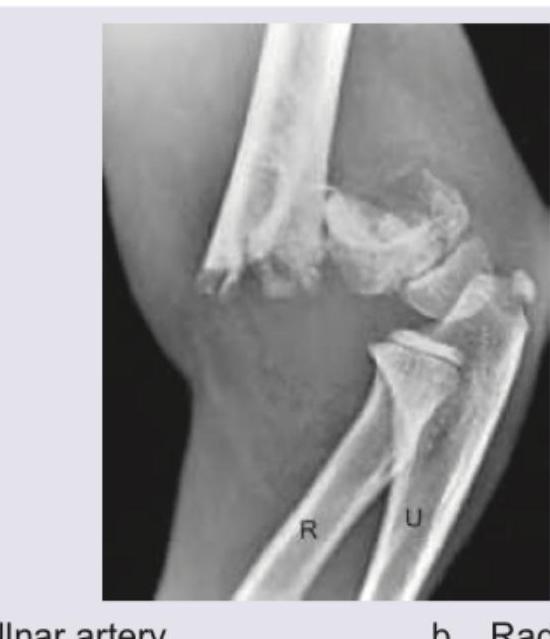

Question 2: A 4-year-old boy fell on outstretched hand. X- Ray is shown below. Which blood vessel is most commonly affected?

- A. Ulnar artery

- B. Radial artery (Correct Answer)

- C. Brachial artery

- D. Cubital vein

Explanation: ***Radial artery*** - The X-ray image shows a **supracondylar fracture of the humerus**, which is a common injury in children who fall on an outstretched hand. - While the **brachial artery** runs anterior to the humeral condyles and is the most commonly injured *major* vessel in supracondylar fractures, the **radial artery** is distal to this area and can be affected by subsequent complications like compartment syndrome or direct trauma from displaced fragments, and is a frequently assessed pulse in these injuries to monitor peripheral perfusion. *Ulnar artery* - The ulnar artery is less commonly affected in supracondylar humeral fractures compared to the brachial or radial arteries. - Its anatomical course protects it somewhat from direct trauma in typical fracture displacement patterns. *Brachial artery* - The **brachial artery** is indeed the most commonly injured *major* vessel in supracondylar fractures due to its close proximity to the distal humerus and its anterior course. - However, the question asks for the most commonly affected blood vessel *following* such an injury, and while direct injury to the brachial artery is a concern, assessment of the **radial artery** pulse is critical for evaluating distal perfusion and identifying potential complications like **compartment syndrome**, which affects blood flow through distal arteries like the radial artery. *Cubital vein* - Veins, including the cubital veins, are generally more pliable and less prone to severe injury or occlusion by bone fragments compared to arteries. - While venous compromise can occur, it is less common and less clinically significant in immediate assessment of these fractures compared to arterial injury.